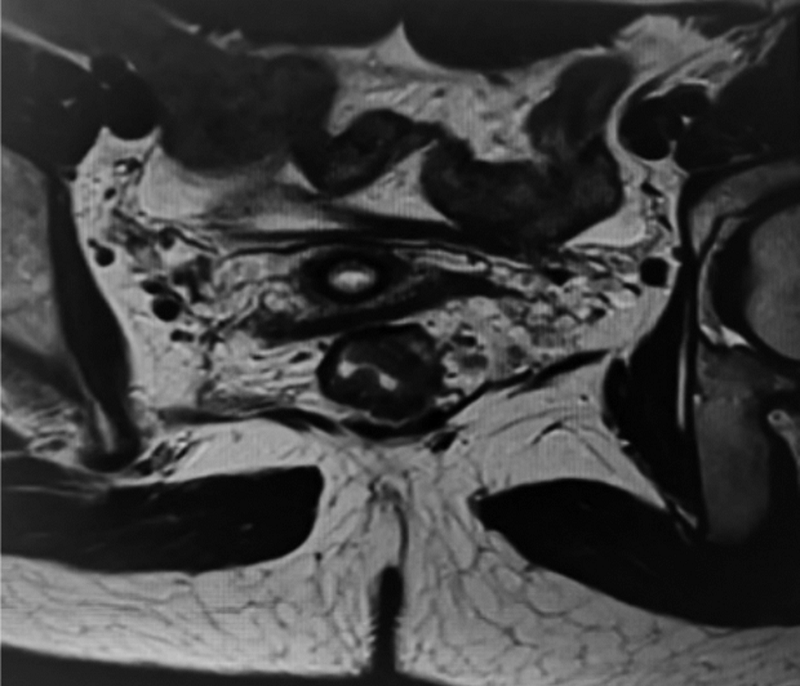

新辅助放化疗对局部晚期直肠癌(LARC)的肿瘤退缩、R0切除、局部控制率、器官保存率等方面均明显优于传统治疗模式,现已成为LARC的新标准治疗方案,但目前仍存在一些具有争议及未解决的问题。现报道1例LARC患者接受新辅助放化疗联合动脉栓塞灌注治疗后再行手术治疗并取得良好效果,这种新辅助治疗模式可供临床参考。